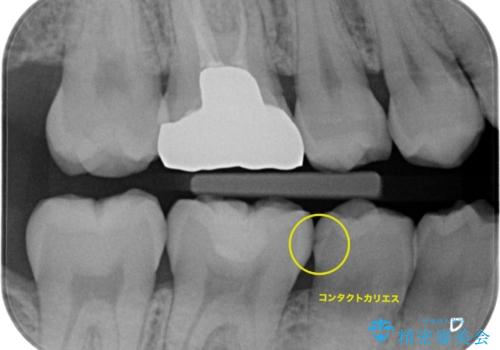

歯と歯の間に虫歯(コンタクトカリエス)がありましたので、拡大鏡下で虫歯を取り、白い詰め物(e-maxインレー)で治療を行いました。

適合の良い詰め物が入りました。